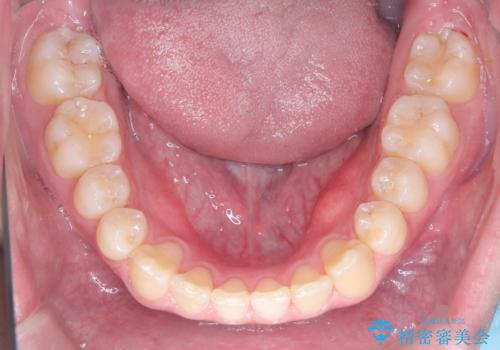

- 八重歯が気になるとのことでご来院されました。お口の中を確認すると、上の前歯がスペース不足で押し出され、少し前に出ている状態でした。抜歯せずに整えるため、奥歯を少しずつ後ろに動かしながら(遠心移動)、歯と歯の間をわずかに削るIPRを行ってスペースを作ることにしました。また、上下の噛み合わせを整えるために2級ゴム(エラスティック)を使用する方針を立てました。

マウスピースを段階的に交換しながら、奥歯を少しずつ後ろへ動かし、八重歯がきれいに並ぶよう調整しました。前歯の突出感を抑えるためにIPRを行い、スムーズに配列。さらに、2級ゴムを活用して噛み合わせも改善しました。治療後は、自然な歯並びになり、笑顔に自信が持てるようになったと喜んでいただきました。